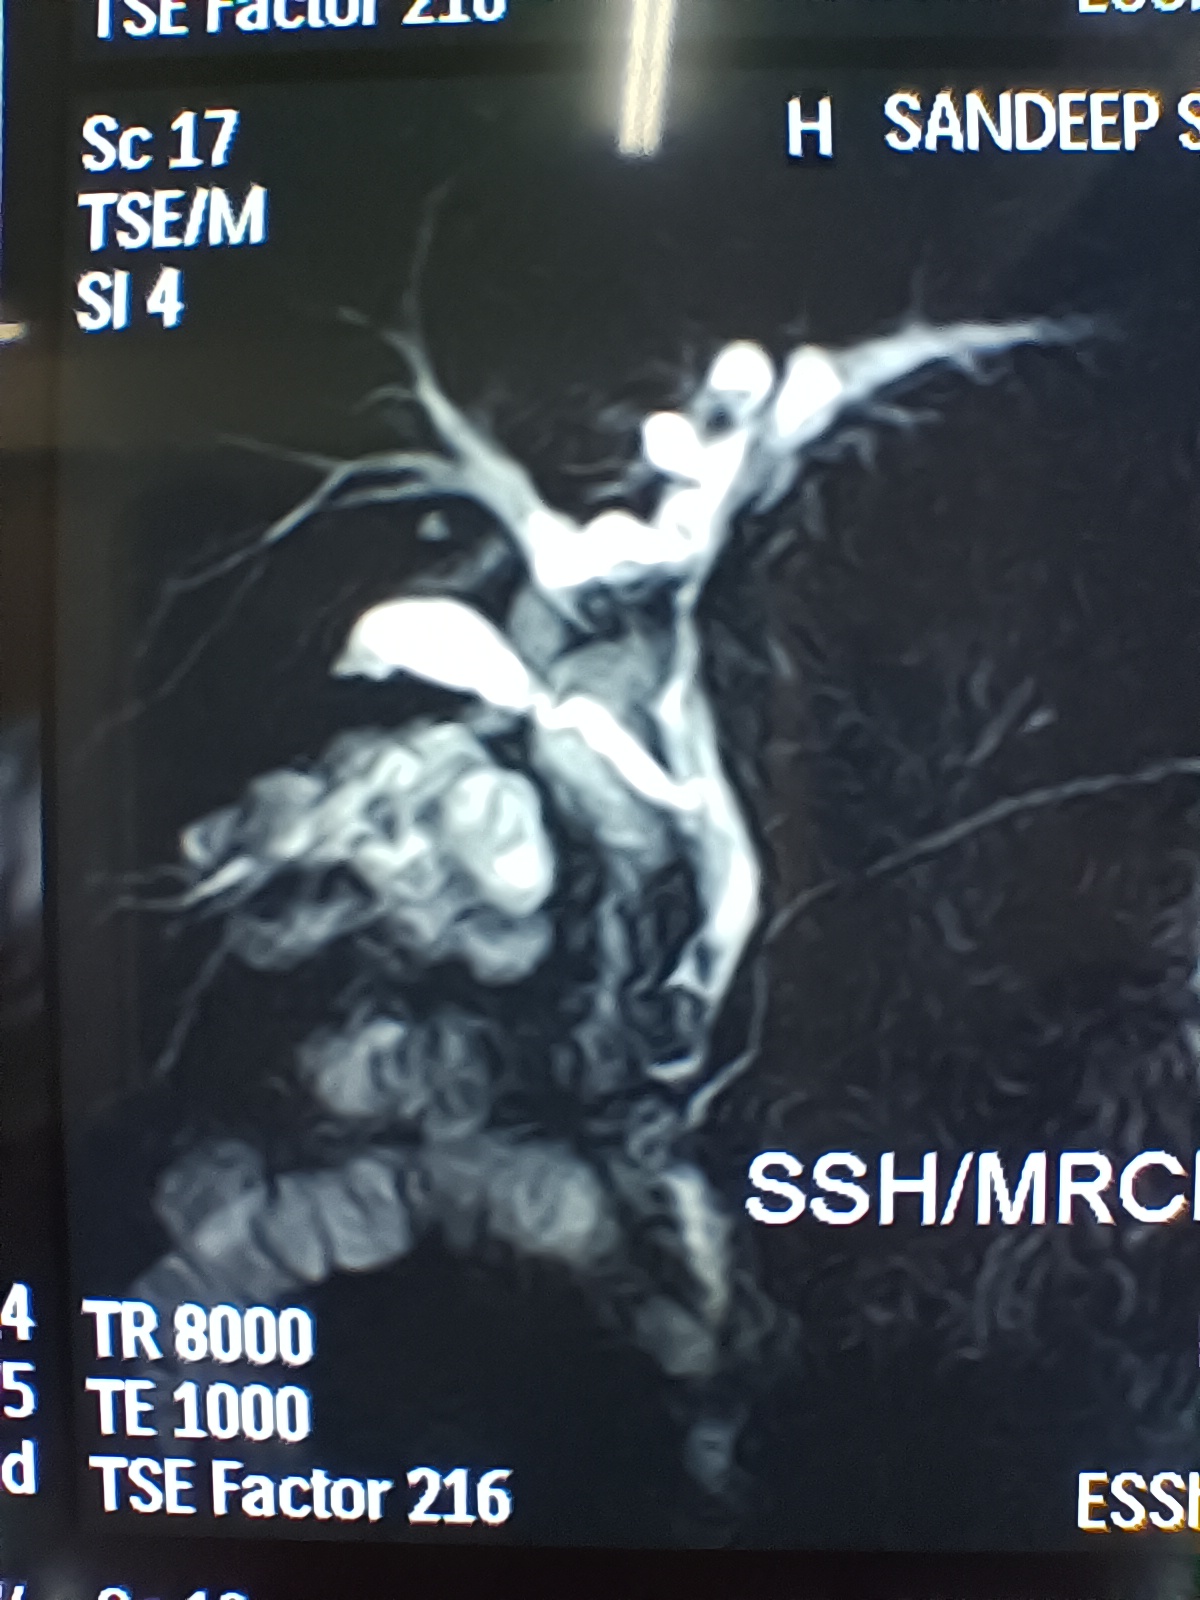

Sandeep singh, 40 years old male patient. Had ERCP, bile duct clearance of stones and stent placed in the bile duct by Dr Arya at Patiala about one and a half years back. Didn’t have cholecystectomy. Presented now with cholangitis. ERCP again, stone and sludge removal from the bile duct and placement of a new stent was done. Lap chole was easy. The ultrasound showed contracted gallbladder, while the MRCP showed a well distended gallbladder and a long cystic duct.